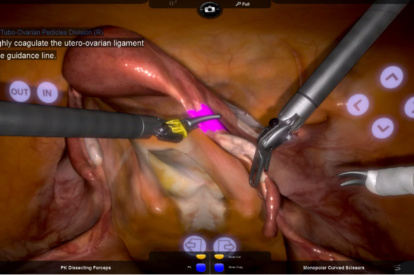

- Highly realistic graphics of human anatomy and simulation of tissue response to instruments

- Interactive task and procedural guidance

- Complication management: simulation of errors and bleedings

- Tutorials: videos of experts performing tasks and procedures on the simulator along with videos of real procedures

Hysterectomy Procedural Tasks Module

Hysterectomy Procedure Module